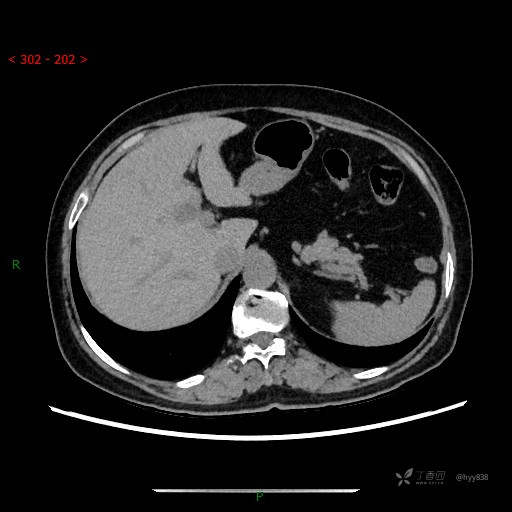

增强动脉期